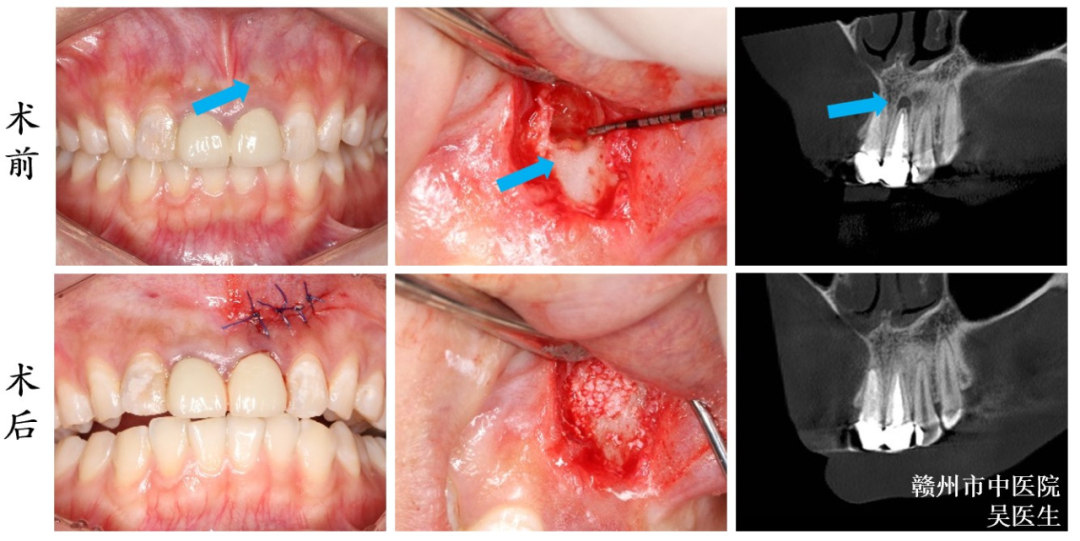

2.CT在颌面部囊肿摘除中的应用

CT检查在颌面部囊肿摘除中发挥着重要作用,CT检查能清晰显示囊肿涉及的根尖范围、涉及的程度、囊肿的范围和周围的重要解剖结构是否有关系,以及囊肿破坏牙根、破坏颌骨的程度。